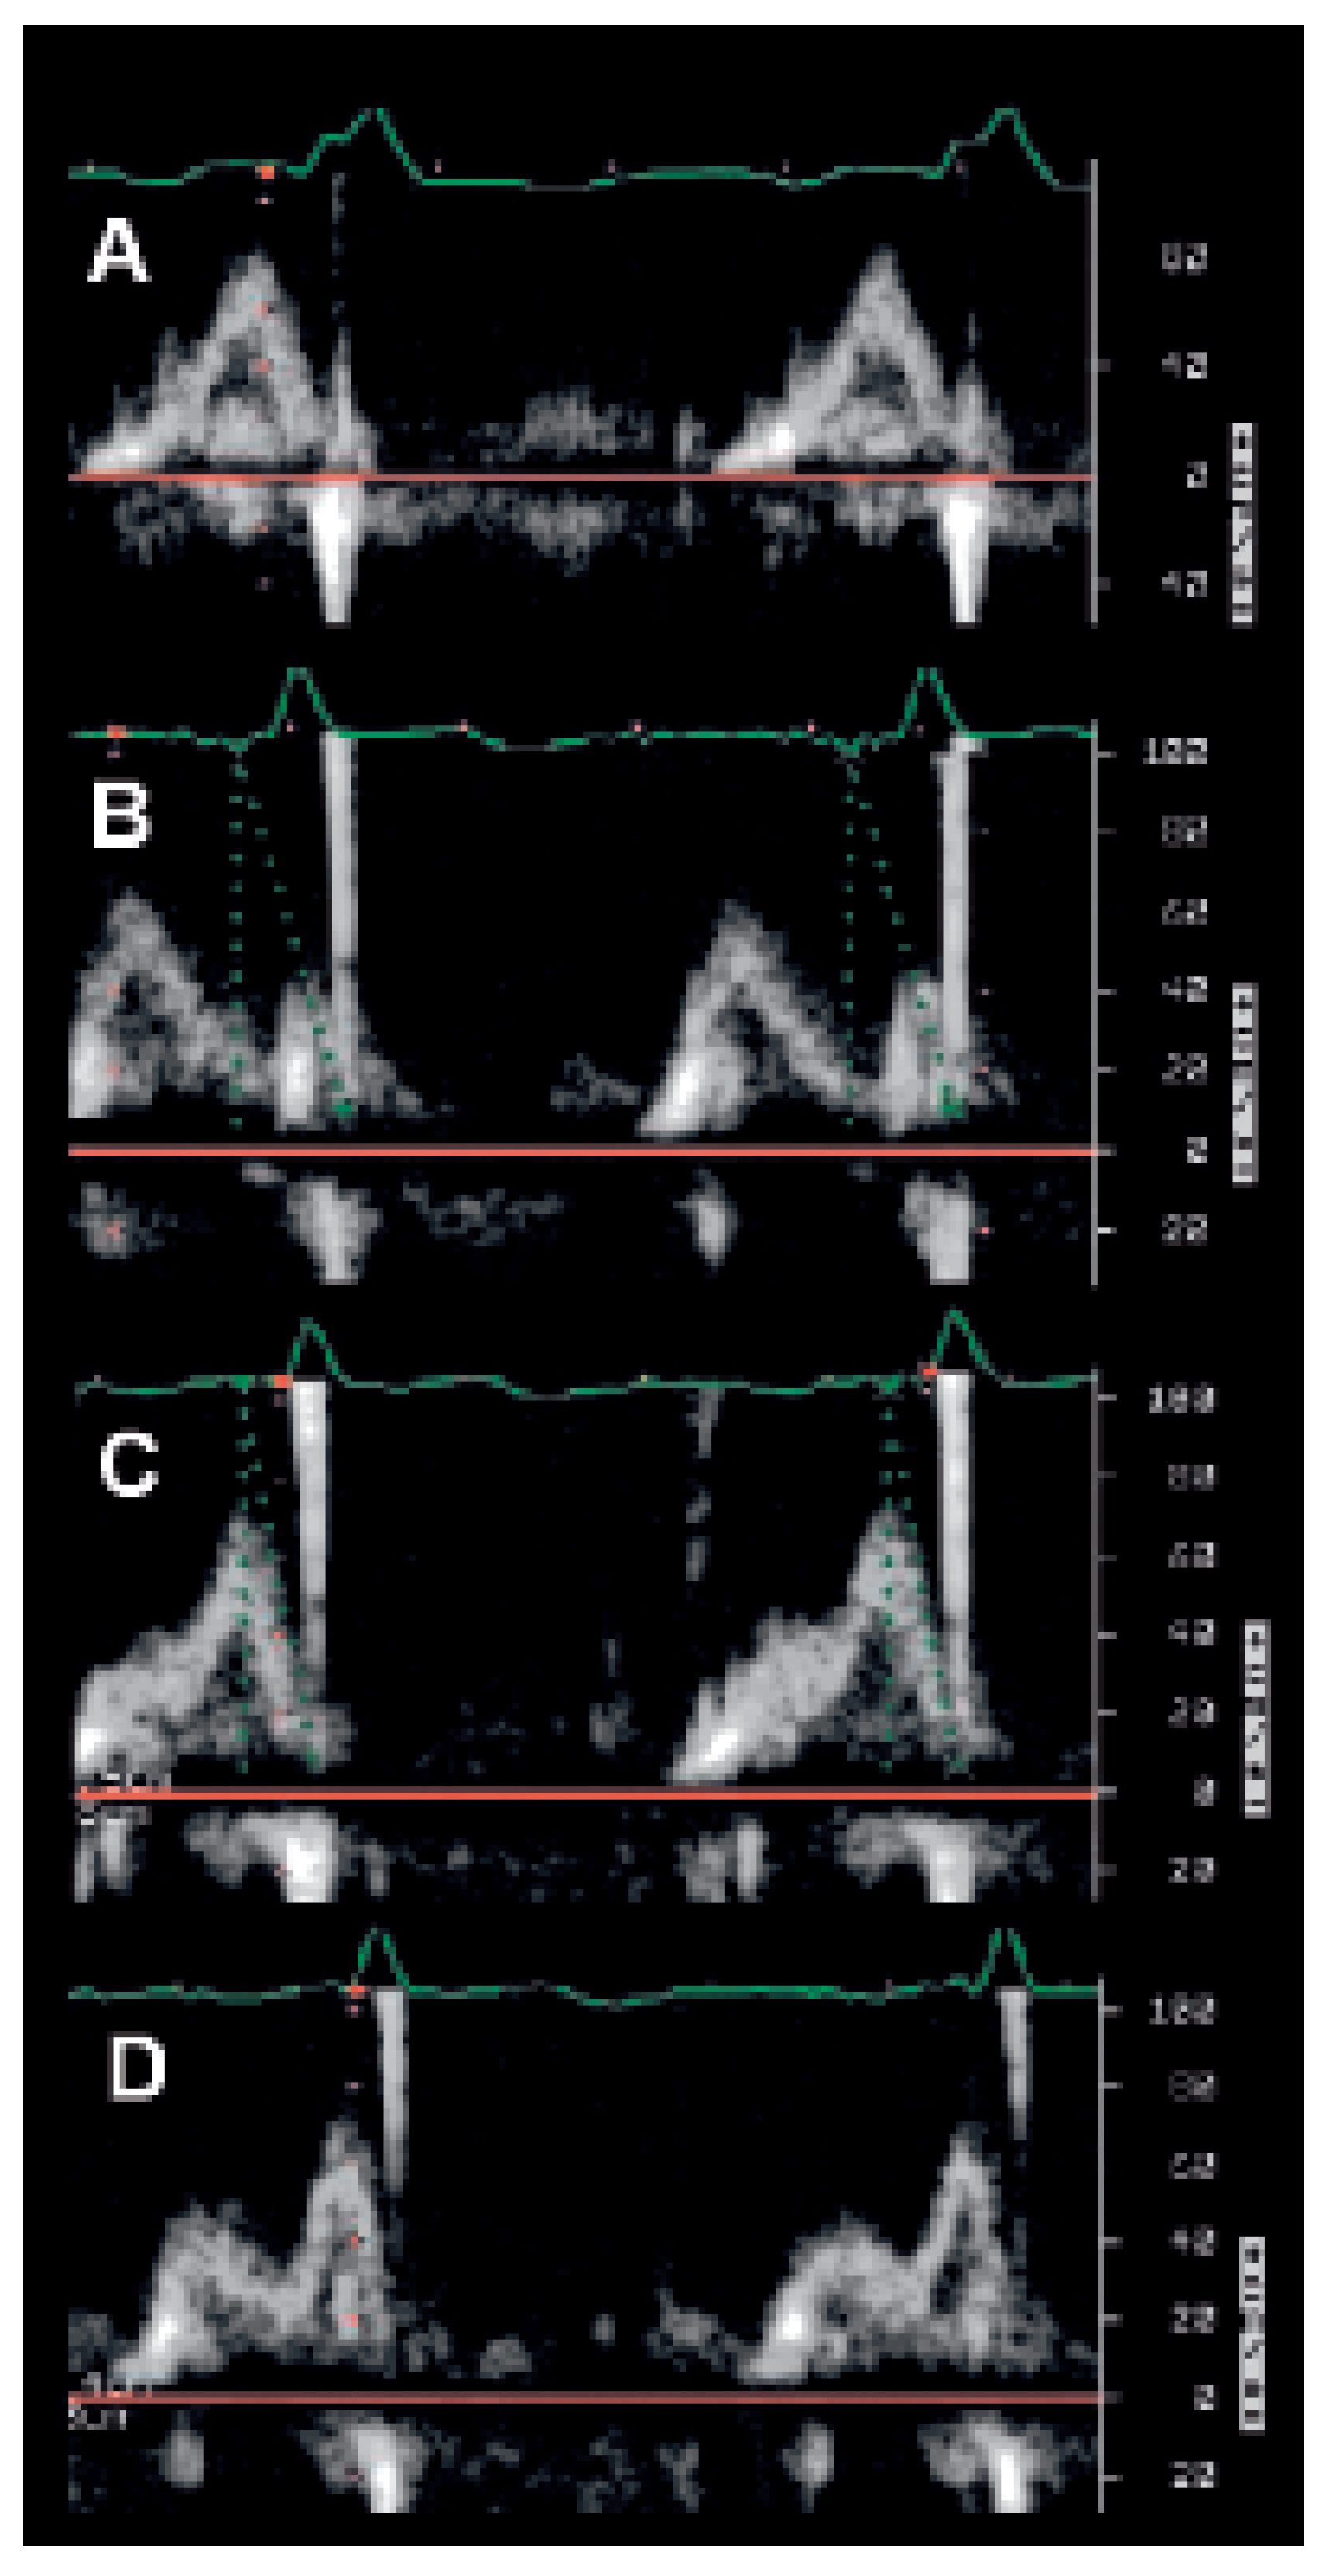

M-mode echocardiography

Conventional Doppler echography